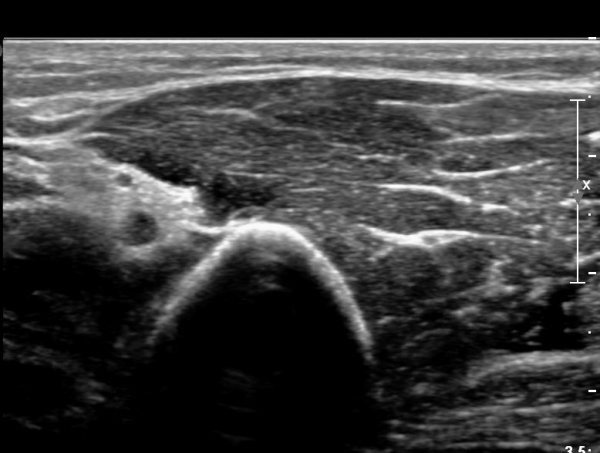

¿ä°ñ °í¶û ¸»´Ü¿¡¼ ¿ä°ñ½Å°æ Á¾´Ü¸é°Ë»ç»ó ¿ä°ñ½Å°æÀÇ Àú¿¡ÄÚ ºÎÁ¾°ú Áß°£ ºÎÀ§¿¡

±¹¼ÒÀû ÇùÂøÀÌ °üÂûµÈ´Ù(»çÁø 5).

¿ä°ñ °í¶û ±ÙÀ§ºÎ¿¡¼ ¿ä°ñ½Å°æ Ⱦ´Ü¸é°Ë»ç»ó ¿ä°ñ½Å°æÀÇ °æ¹ÌÇÑ Àú¿¡ÄÚ ºÎÁ¾ÀÌ °üÂûµÈ´Ù(»çÁø 6).